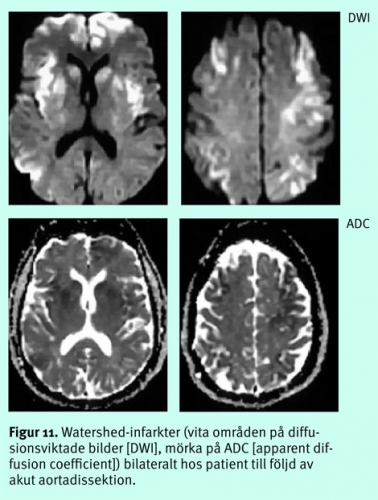

Diffus hjärnskada efter djup anoxi/hypoxi eller excessivt lågt systemblodtryck, tex efter hjärtstillestånd, status asthmaticus, kolmonoxidförgiftning, grav hypovolemi etc, ger, om den inte är letal, en selektiv skada på vissa neuronpopulationer, framför allt på dem med högst krav på energitillförsel, dvs i basala ganglier, i kortex känsligaste lager (3, 4 och 5), hippocampi, thalami mfl (Figur 10), ibland i watershed-områdena (Figur 11) [13].

Sedan decennier vet vi att skador av global ischemi ibland kan visualiseras med DT subakut och att de vanligen blir tydligare efter 3–4 dagar. Diffusionsviktade bilder är ett betydligt känsligare instrument för att påvisa globala hypoxiska/ischemiska förändringar, men den kliniska nyttan är ofta begränsad. Radiologen kan sällan infria intensivvårdsläkarens förhoppningar om säker prognostisk information om huruvida ett permanent vegetativt tillstånd är att vänta, eftersom någon entydig gräns mellan förändringar som kan vara förenliga med återhämtning och irreversibla skador inte finns, inte ens med denna teknik. Utbredda, kraftiga förändringar i basala ganglier kan dock ge en fingervisning om ett dåligt neurologiskt utfall.

Någon gång kan DWI förbättra förståelsen av en komplicerad intensivvårdssituation och tex ge indicier på om hypovolemi/lågt perfusionstryck eller hypoxi varit väsentliga orsaker till det kliniska tillståndet.